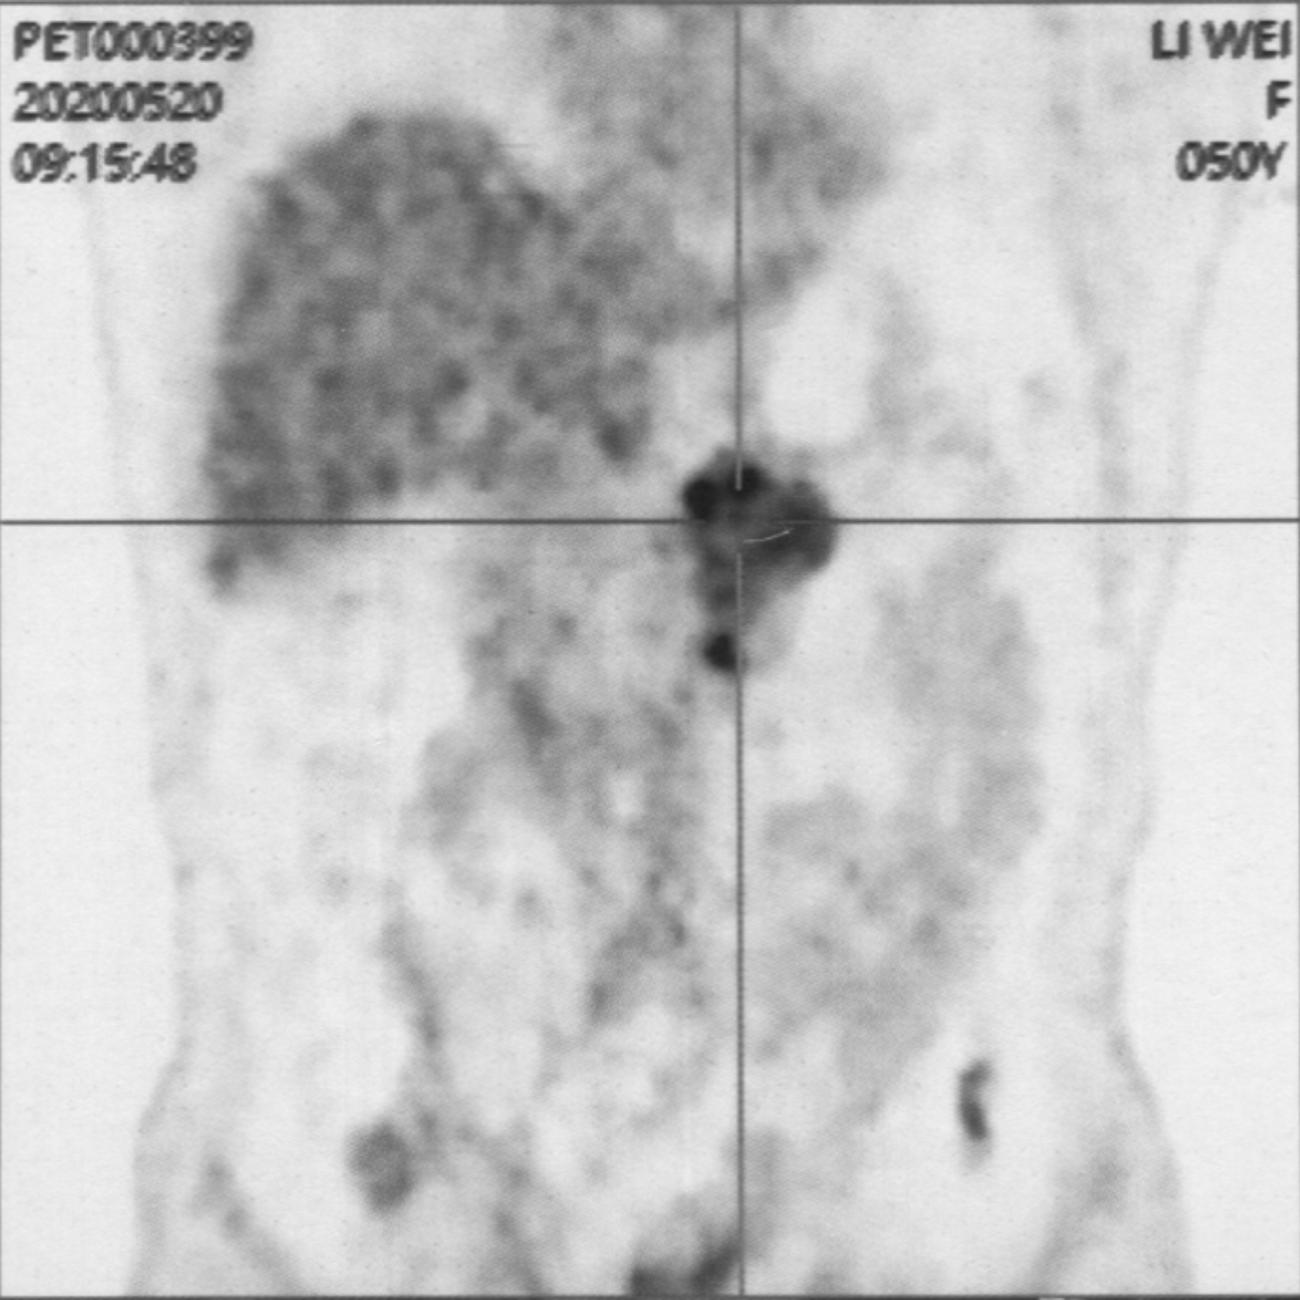

The word “stop” contains the essence of photography because the freeze-frame can describe death. In contrast, photography is a subjective behavior when pausing the stop key. In this way, when the on-camera scene and the content contained, that is the stopped life co-frequency, will form a cycled looped in stop status. Among them, the frozen time and the frozen life raise the question of what death is. What are Death Images? How do we prove the dialectical and contradictory relationship between the end of life and the preservation of photography? When mentioning something related to death in daily life, people tend to hide the truth and lie to each other. After a photographer’ s mother died of breast cancer and pancreatic cancer in the late stage, the father and maternal grandmother, as family members, chose to hide the close relationship that had broken after the mother's death, and decided to quickly move out of the old house where they had lived together. Although the pain and sorrow are obvious, they choose to avoid and ignore them. However, photography, as an upward channel with expansion properties, carries a private space that fits between the images of life and death, thereby generating natural resonance. Starting from her self-consciousness, the photographer decides to reveal the truth of death in daily life, capturing and documenting her mother's process of passing, and organizing the pathological imagery from her mother's illness to death. Subsequently, the photographer took images of family members and the old house, attempting to break the barriers and obstacles that create a disconnection between herself and the external world regarding the topic of death and intimate relationships. “Lies in stopping” employs a clock as a metaphor and link, connecting the themes of time and life, linking the beginning and stasis of time with the blossoming and ending of life, prompting contemplation on the notion that life resides in stop. This practice explores new pathways to sort through and reconstruct family relationships through photography after losing a loved one. It also establishes a visual space for discussion between the audience and themes of death, body, and family, promoting a positive and constructive cycle. Furthermore, it emphasizes the healing function of imagery concerning the psychological and emotional trauma carried by death.

The artist chooses to “immortalize” her mother’s illness and passing, turning the camera toward a subject that many prefer to avoid. Death remains traumatic precisely because we fail to justify or rationalize it; forgetting often feels easier than confronting its emptiness. After her mother died of late-stage cancer, the photographer witnessed how family members tried to distance themselves from pain—moving out of the shared home, silencing grief, choosing removal over remembrance. Instead, the artist does the opposite: she decides to give death a face, creating images in which others might see echoes of their own losses.

Lies in Stopping documents not only the mother’s physical decline but also the emotional architecture of relationships reshaped by death. Yuehan Hao attempts to dismantle the barriers that prevent individuals from acknowledging death and its impact on intimacy.